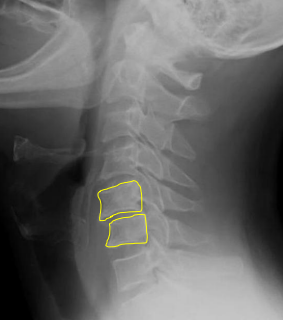

AP Open Mouth: Is this Image Good?

No.

Base of skull superimposed over dens and lateral masses

Atlantoaxial joint is not clearly demoed

Extensive extension of skull

Reposition by slight flexion of the neck or angle the CR slightly caudal